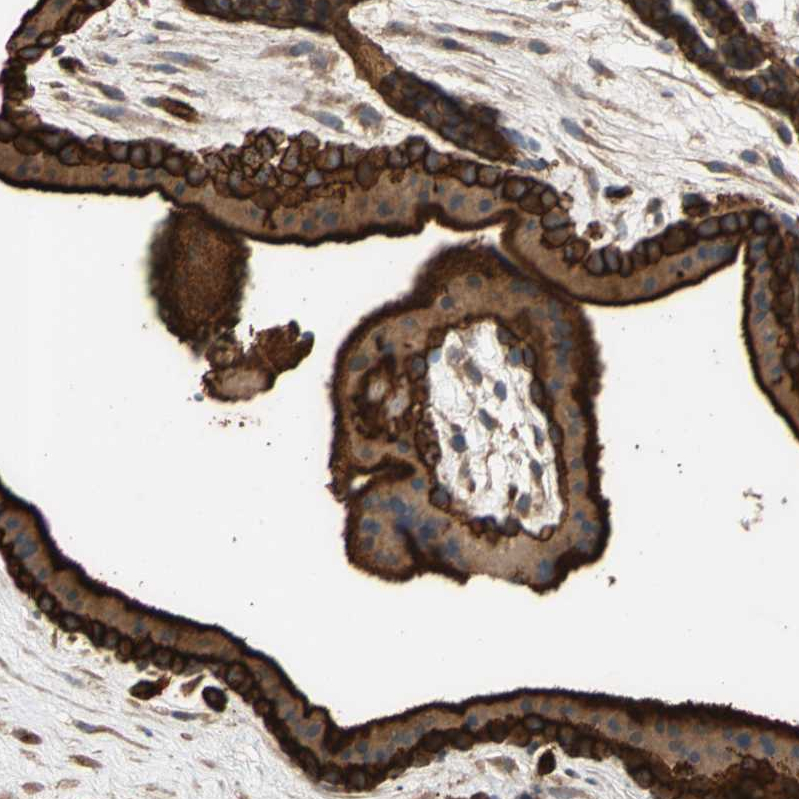

Immunohistochemical staining of human tonsil shows strong cytoplasmic positivity in germinal center cells.